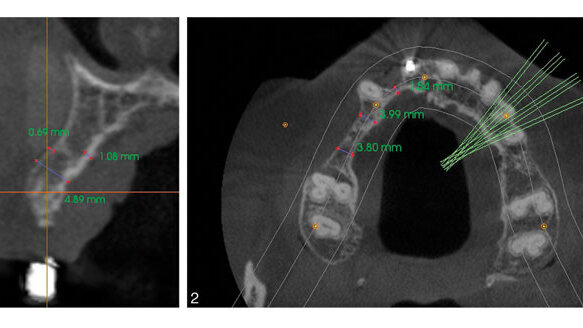

Implant treatment for full-arch fixed restorations has been around for decades now.1–3 The treatment usually involves four to six implants placed in ...